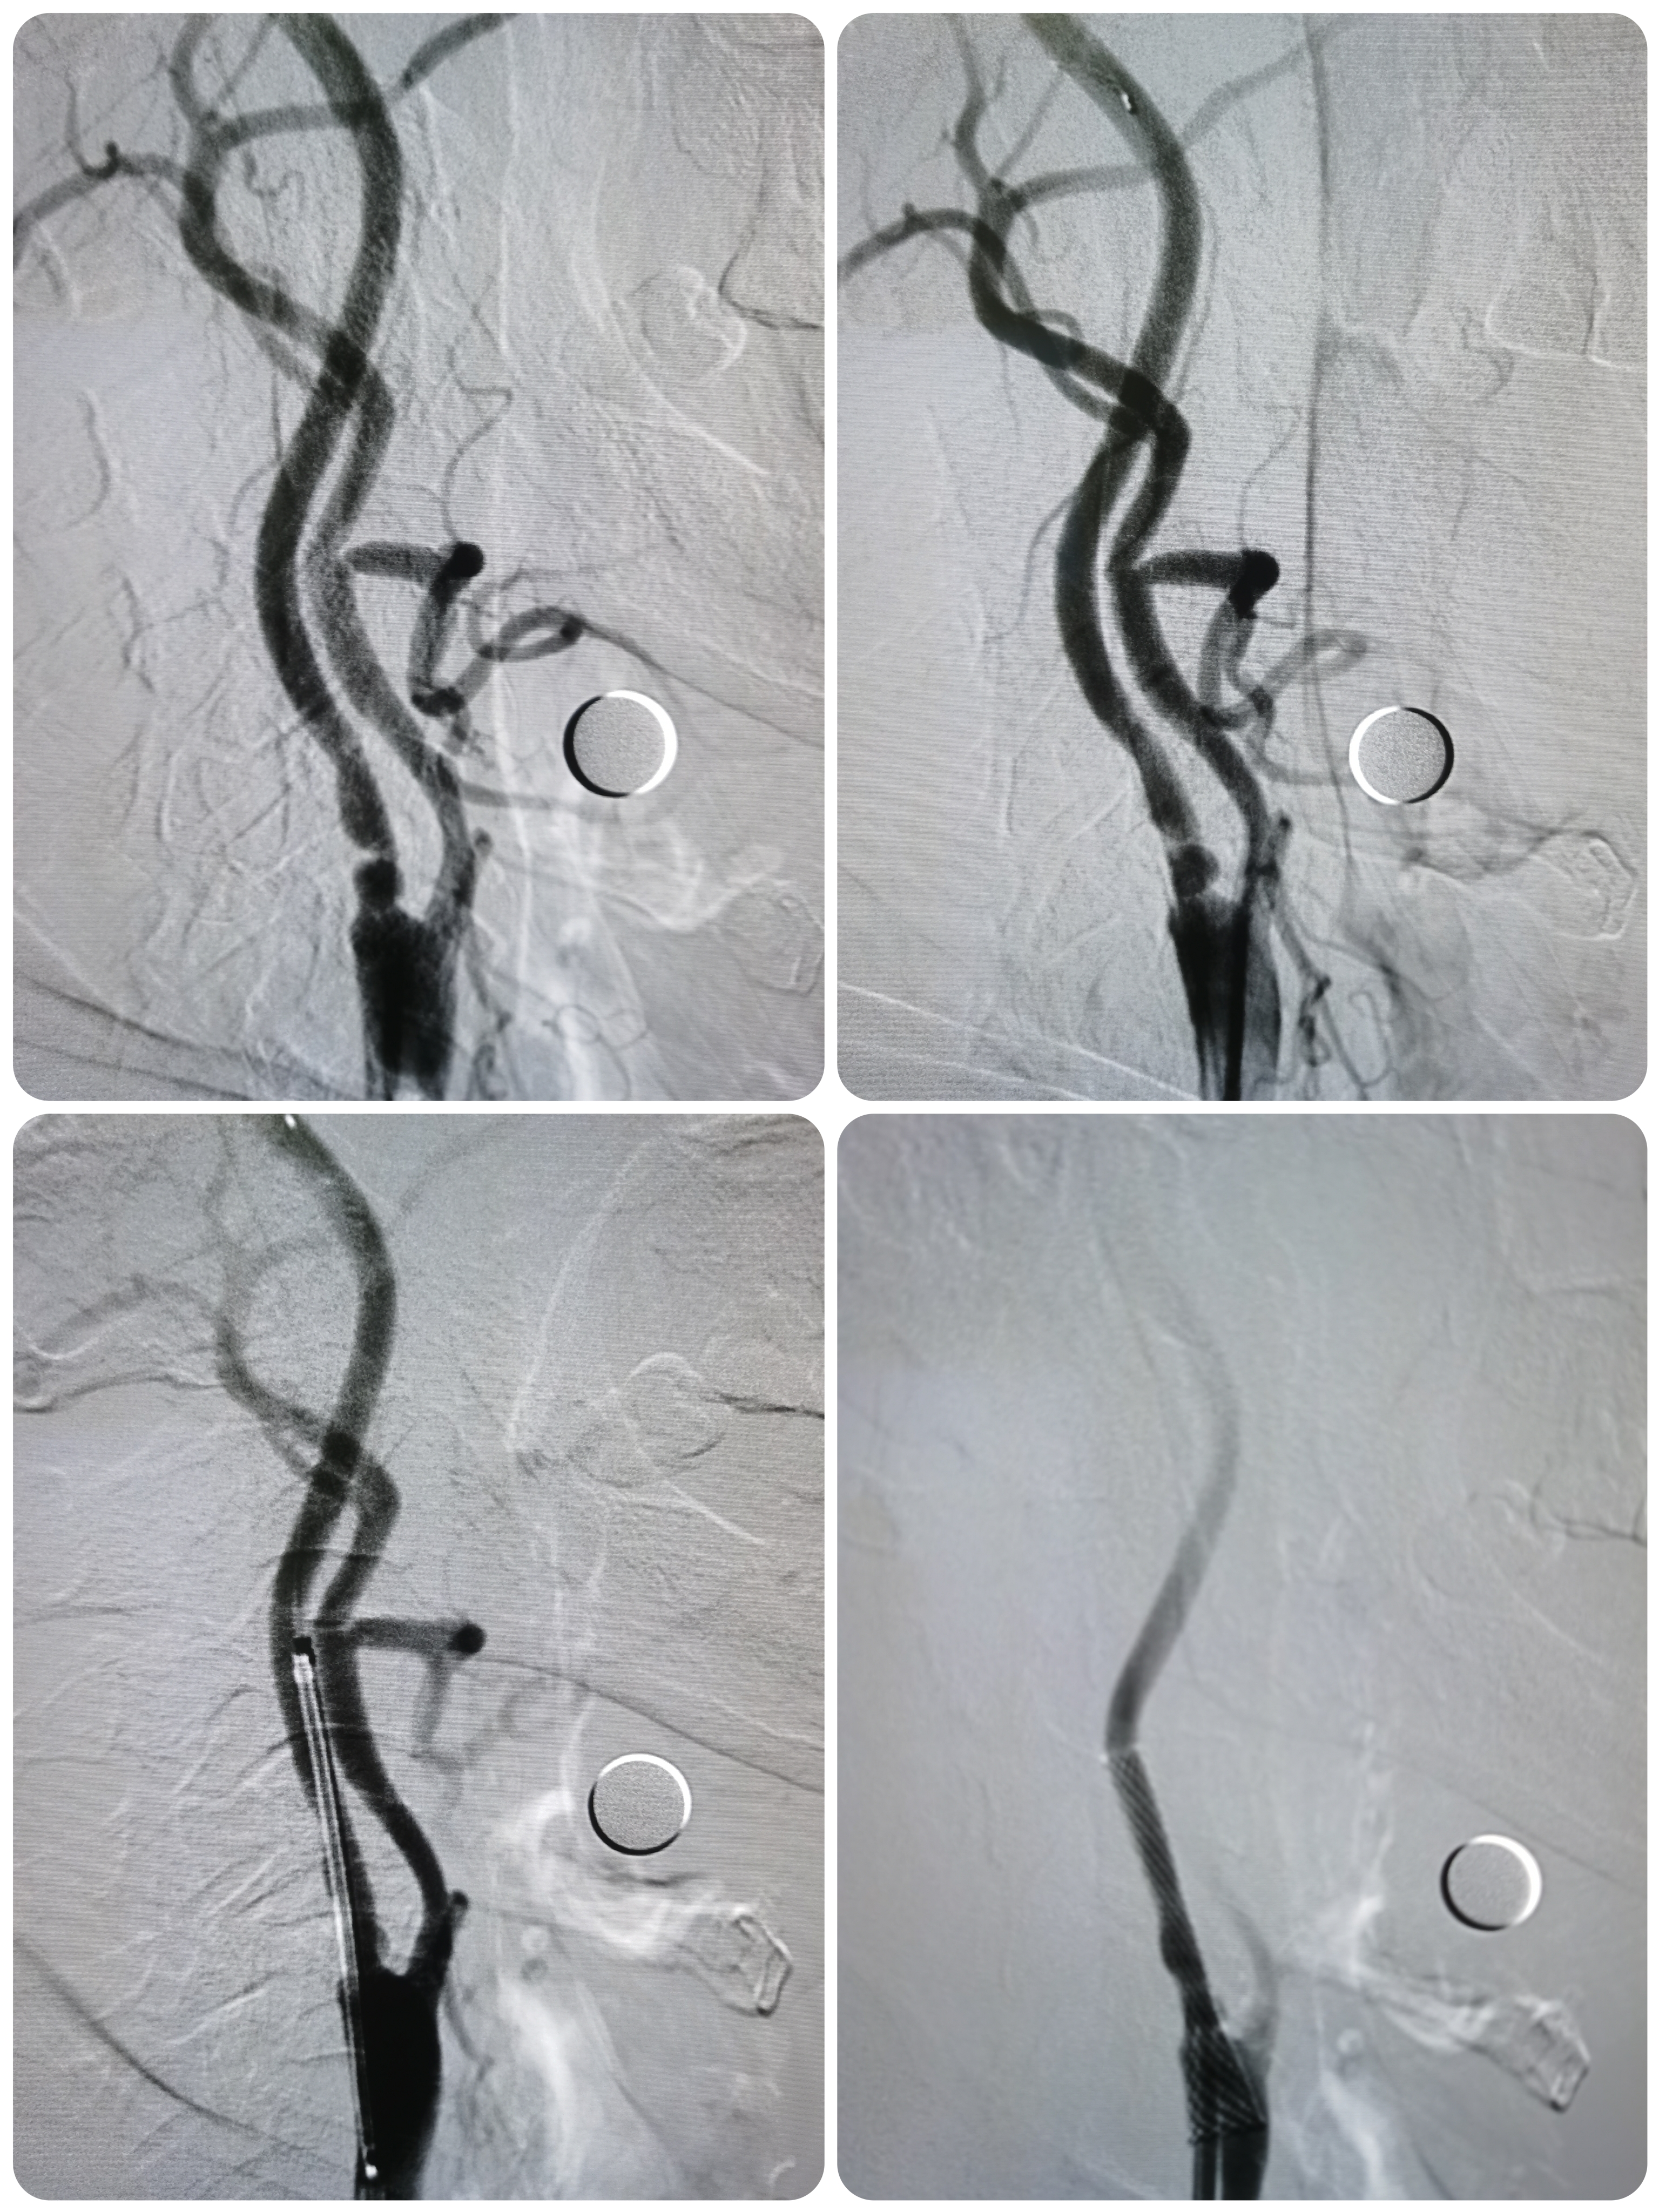

左侧颈内动脉狭窄伴溃疡形成。

患者双侧颈内动脉狭窄,右侧线性狭窄,左侧重度狭窄伴溃疡形成,均局部介入治疗指征,是分期处理还是同期处理双侧颈内动脉狭窄均有优缺点,综合分析评估后拟同期处理,术后便于管理血压。

将导引导管调至左侧颈总动脉末端,远端置入保护伞。

9/30支架定位。

支架释放后狭窄改善,覆盖不稳定斑块。

支架释放后颅内血供良好。

颅内血供良好。

2、同期处理双侧颈内动脉可便于术后积极控制血压,避免出现高灌注出血,但也存在严重窦反射可能,患者先行右侧颈内动脉支架后未见明显窦反射,遂同期处理左侧颈内动脉。